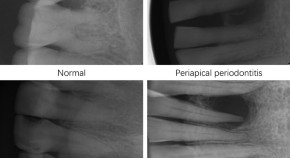

Artificial Intelligence-Powered Clinical Decision Support and Simulation Platform for Radiology Trainee Education